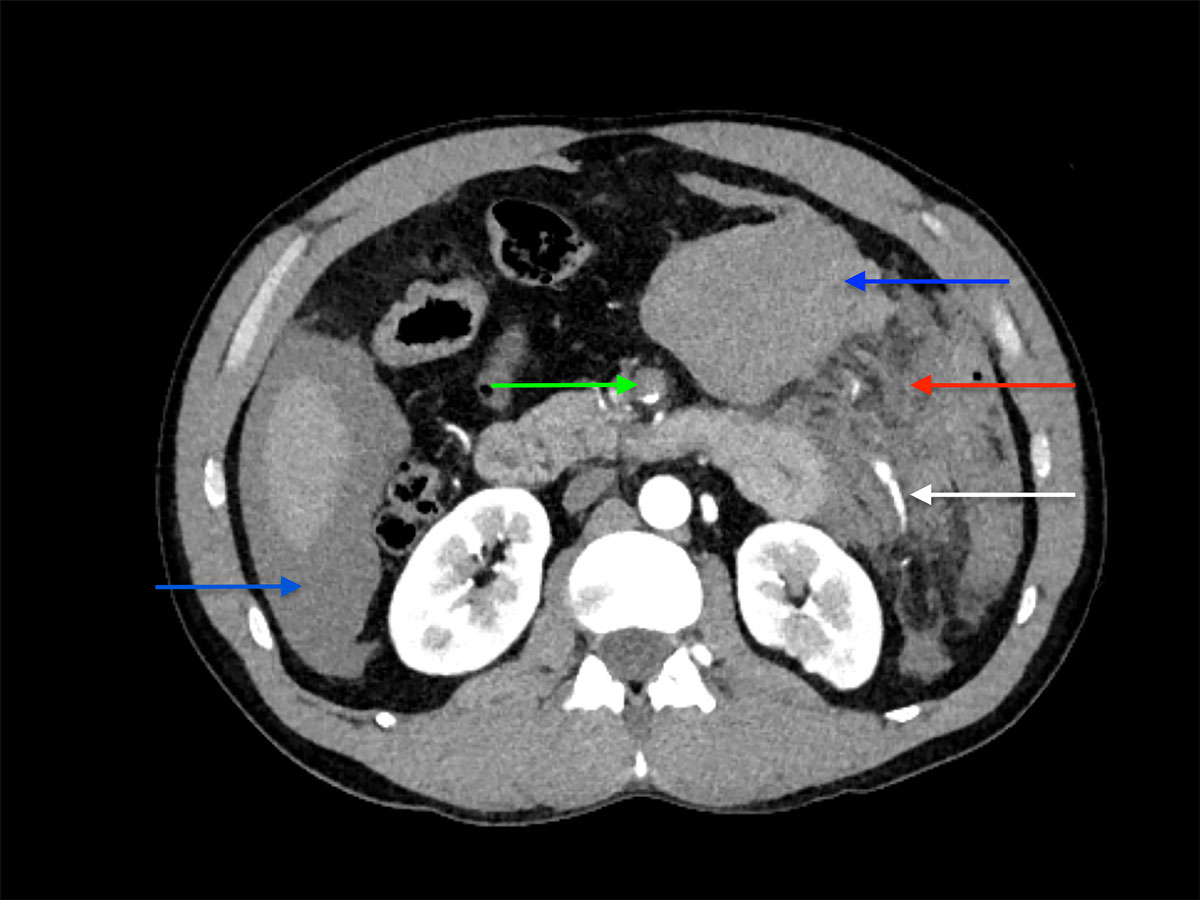

A 42-year-old male was admitted to our emergency department with acute abdominal pain, lipothymia and nausea. The patient was tachycardiac and hypotensive. Physical examination revealed signs of peritonitis. His bloods showed elevated lactates, at 4 mmol/l, while haemoglobin level was normal. The abdominal computed tomography (CT) angiography revealed a massive haemoperitoneum from a ruptured aneurysm of a distal branch of the ascending left colonic artery (fig. 1). Moreover, several aneurysms and strictures of the main intra-abdominal arteries were found, including dissections of both the superior mesenteric and the left common iliac arteries (figs 2 and 3 ).

Figure 1 Emergency abdominal CT scan showing massive haemoperitoneum (blue arrows), dissection of the superior mesenteric artery (green arrow), misty aspect of the mesentery of the left colon (red arrow) and pathological ascending branch of the left colonic artery with strictures and aneurysms and without contrast blush (white arrow).